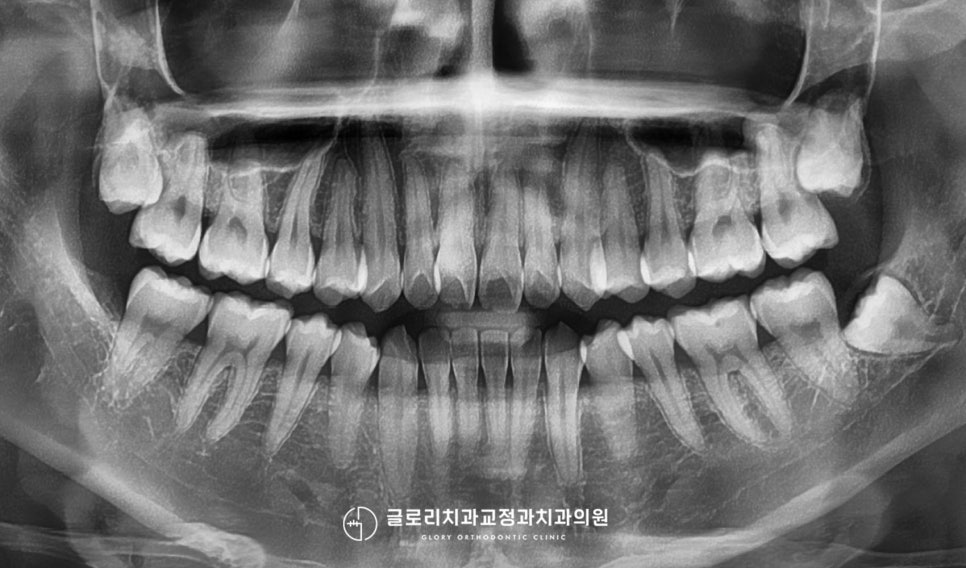

환자가 가지신 문제점이

앞니 틀어짐이었기 때문에

전치부를 포함한 소구치 부위까지

8개를 부착해 와이어로

연결을 도와드렸습니다.